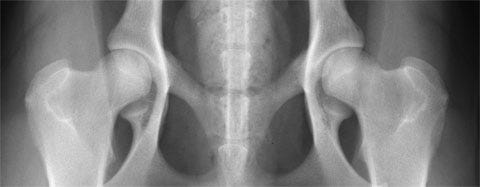

HD- ED- reading fee dogs from Iceland

How to order and pay for evaluation of x-rays of dogs living in Iceland.